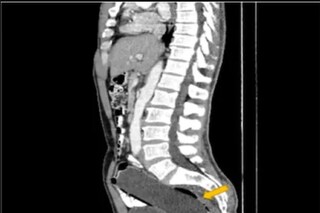

ব্যথায় কাতরাতে থাকেন ওই ব্যক্তি। অবশেষে ওই ব্যক্তির স্ত্রী তাকে নিয়ে ডাক্তারের কাছে যান। ডাক্তার সবটা শুনে সিটিস্ক্যান করার পরামর্শ দেন। এবং ব্যক্তিকে সঙ্গে সঙ্গে হাসপাতালে ভর্তি করে নেন। এর পর ওই ব্যক্তির তলপেট, রেকটাম স্ক্যান করা হয়। স্ক্যানের রিপোর্ট দেখে মাথায় হাত সকলের। চমকে যান ডাক্তার নিজেও। বুঝে পাচ্ছিলেন এ কী করে সম্ভব! যা জানলে আপনিও অবাক হবেন বইকি! ওই ব্যক্তির রেকটামে ঢুকে রয়েছে এক অদ্ভুত জিনিস। কিন্তু কি করে সম্ভব? তা নিয়ে প্রশ্ন থাকলেও, সামাধান হয়।

সিটি স্ক্যানে জানা যায় ওই ব্যক্তির রেকটানে সাত ইঞ্চির একটি জলের বোতল ঢুকে রয়েছে। আর এই বোতল থেকেই অসহ্য ব্যথা হচ্ছে তার। সময় নষ্ট না করে অপারেশন করার সিদ্ধান্ত নেন ডাক্তাররা। খুব সতর্ক ভাবে বের করে আনা হয় সেই বোতল! পাঁচ দিন পর তাকে হাসপাতাল থেকে ছেড়েও দেওয়া হয়। কিন্তু রেকটামে বোতল কী ভাবে এল তা নিয়ে চাঞ্চল্য তৈরি হয়। অবাক হন ডাক্তার এবং ওই ব্যক্তির স্ত্রী! জানা যায় ওই ৫০ বছরের ব্যক্তি বিকৃত কামের শিকার! যৌন উত্তেজনা পেতে নিজেই ওই বোতল রেকটামে ঢুকিয়ে দেন ব্যক্তি। ভেবেছিলেন বেরিয়ে যাবে নিজে থেকে। কিন্তু তা হয় না! ভয়ে ওই ব্যক্তি কাউকে কিছু বলতে পারছিলেন না। তবে খবর জানাজানি হতেই ভাইরাল হয়।